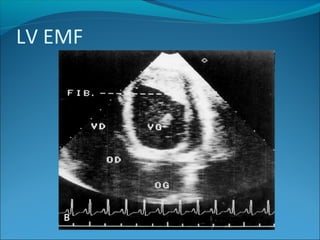

Features of LV EMF –

Involvement of the posterior cusp and the posterior

papillary muscle (unlike in RHD , AML is spared)

Obliteration of LV apex

Presence of areas of dyskinesia and aneurysmal

dilatation

Bidimensional echocardiographic apical two-chamber view of a patient with left-

sided EMF (top, a) and a four-chamber view of a patient with right-sided EMF

(bottom, b)

LV EMF

LV EMF – apical fibrosis , PML

tethering 70